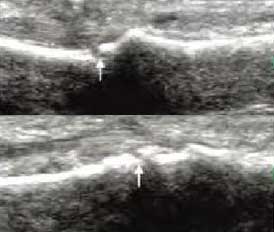

4、具备软组织超高分辨率 区分关节受损层级

肌骨超声通过平面成像能力发现RA关节软骨微小病变,早期就能准确反映出软骨下骨质线回声增高程度,关节软骨表面是否毛糙模糊凹凸不平、形态是否规则、有无明显隆起或缺损形成,判断早期RA软组织改变及RA骨质受损状况。

Ⅰ级

骨表面欠平整骨关节面边缘不整齐、模糊,形成不规则间隙

Ⅱ级

骨质中断或缺失骨表面出现弧形条状低回声,软骨表面不规则变薄、缺损形成

Ⅲ级

骨表面凹凸不平骨表面缺损融合成广泛的骨质破坏、侵蚀